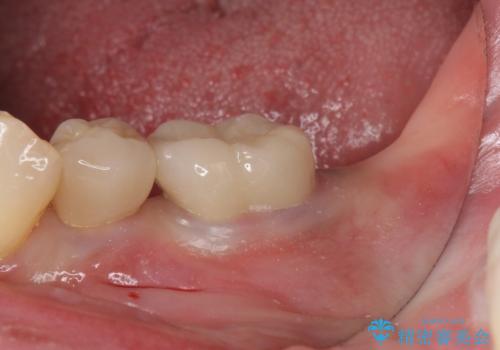

右の奥歯を機能回復|再根管治療とインプラントでしっかり噛める歯へ